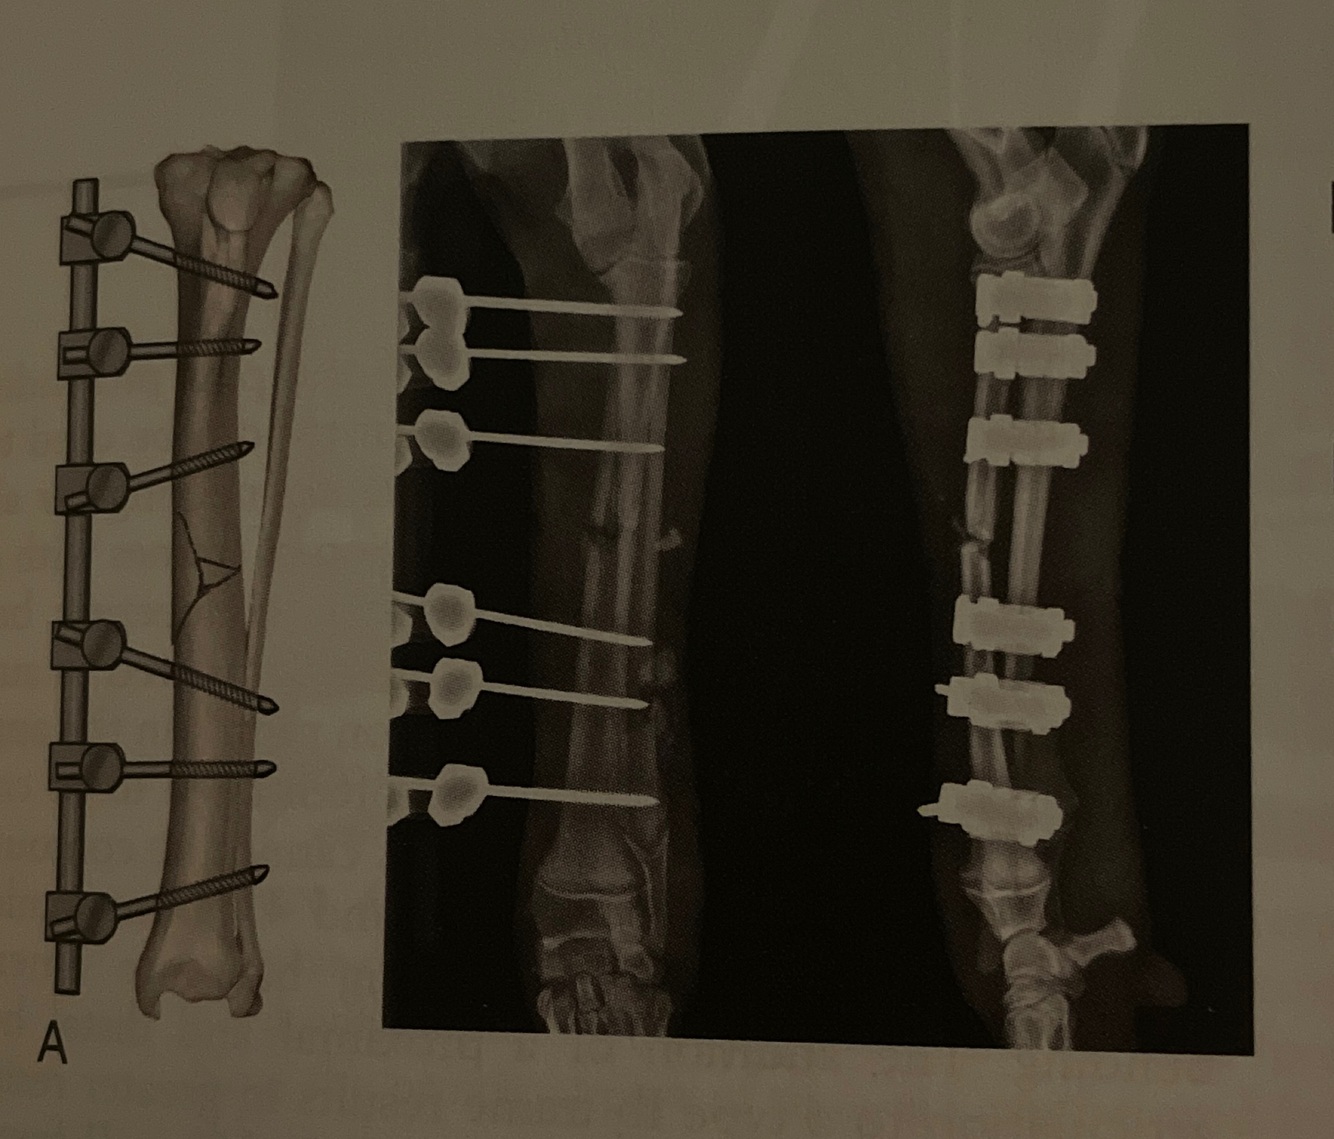

Type: Ia

Pins: Half

Connecting Bars: 1

Pin Geometry:

-Unilateral uniplanar